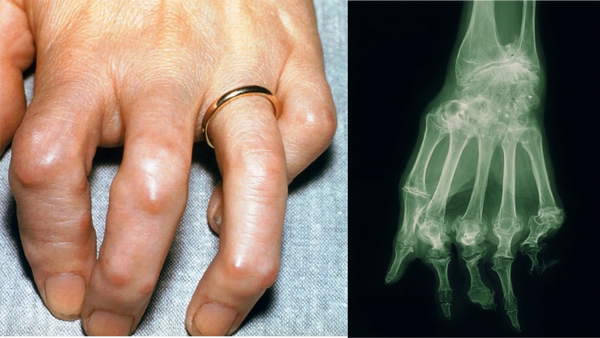

Chronic inflammation can damage cartilage, increase stiffness, and reduce mobility. For those with osteoarthritis or other degenerative joint issues, high CRP, TNF-alpha, and IL-6 levels can accelerate joint degeneration, intensify pain, and limit daily activities.